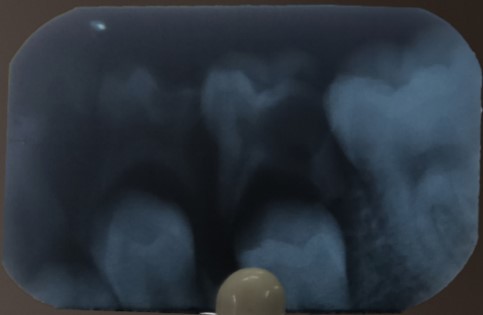

Radiographic contraindications

- External root resorption with less than two-thirds of primary root structures remaining.

- Within root resorption at the root's apical third.

- In the case of radicular cyst.

- Intraradicular radiolucency that communicates with the gingival sulcus.

- Pathologic condition extending to developing permanent tooth bud.